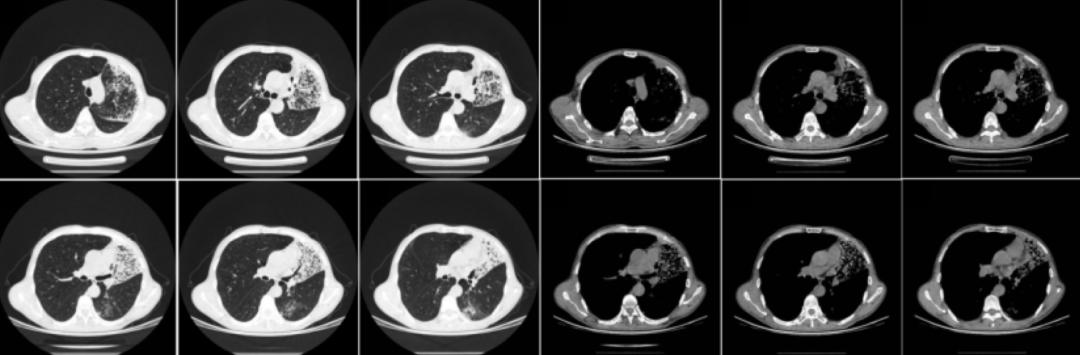

对其辅助检查的情况为:ESR 24mm/h,超敏C反应蛋白10.6mg/l,血常规、降钙素原、凝血、内毒素、真菌D-葡聚糖、半乳甘露聚糖肽、支原体、衣原体、嗜肺军团菌抗体、肝肾功、电解质、心肌酶、电解质均正常;结核感染T淋巴细胞检测阳性,结核杆菌抗体、结核杆菌DNA、PPD试验阴性;自身抗体、抗中性粒细胞抗体、风湿系列阴性;肿瘤标志物NSE 18.25 ng/ml(正常值0—16.3ng/ml);血气分析(FiO2 21.0%)示pH 457、pO2 59.9mmHg、pCO2 31.7mmHg、SaO2 92.0%。以下为该患2019年5月22日胸部CT的影像学资料:

胸部CT提示两肺可见片状密度增高影,以右肺为主,其内可见支气管充气征,两肺斑片状磨玻璃及稍高密度影,并纤细网格状影,呈铺路石改变。

入院后考虑到患者病史已达半年之久,辗转多家医院就诊,反复抗炎治疗,效果不佳,入我科后给予强效广谱抗生素美罗培加强抗感染治疗,并在治疗后复查血气分析,呼吸衰竭纠正后,于2019年5月23日行支气管镜检查,镜下可见:双侧支气管系统大量透明泡沫样分泌物溢出,右侧为著,左下叶背段支气管管口炭沫样沉积,右下叶支气管粘膜镜端触之易出血,各管腔通畅,未见肿物及狭窄,结合影像学,在右上叶前段及尖段活检。

2019年5月22日:

2019年11月11日: